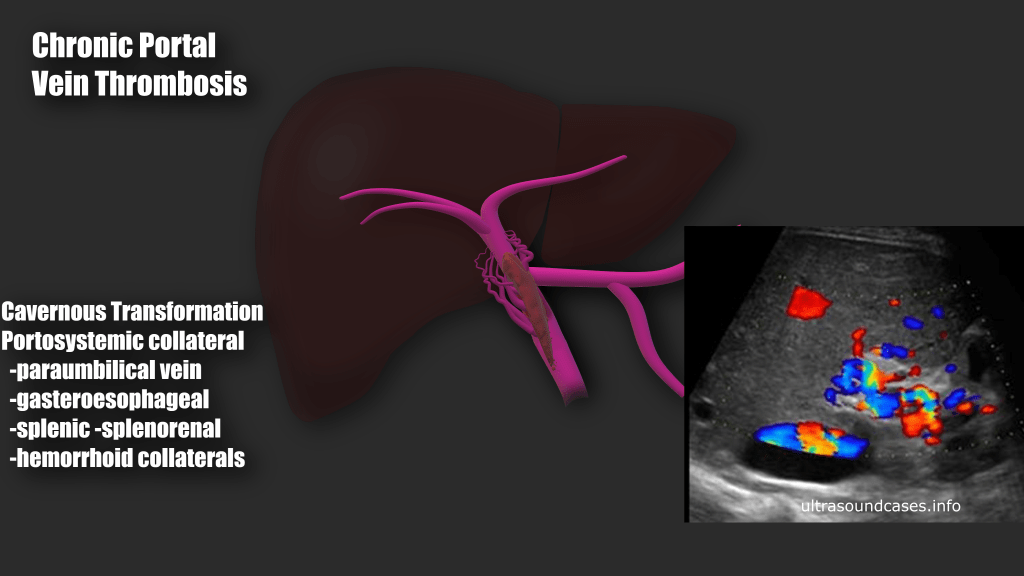

Approximately 25% of cirrhotic patients can develop portal vein thrombosis, Oftentimes due to portal hypertension and sluggish flow through the fibrotic liver. Stagnant blood flow is more prone to coagulation. Any hypercoagulable condition can lead to portal vein thrombosis. (i.e. cancer, pregnancy, coagulopathies, COVID 19 to name a few).

Many people diagnosed with PVT are asymptomatic, some patients may have ascites, abdominal pain, hepatosplenomegaly, blood in the stool, bloody emesis (from ruptured varices). When the thrombus causes portal hypertension or if there is portal hypertension form cirrhosis, portosystemic collaterals may form. These sites of include:

- Esophageal varices

- Gastric varices

- Recanalized paraumbilical vein

- Splenic varices and splenorenal shunt

- Rectal varices and hemorrhoids